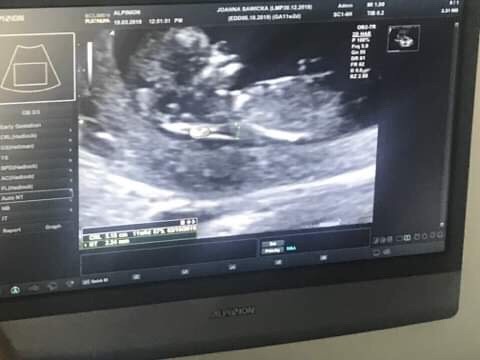

Tak dla pewności przed wyjazdem wskoczyłam dziś na wizytę i maleństwo rośnie pięknie podwoiło swoje rozmiary przez 2 tyg. wiec ma 52mm :) i według USG 11t7d No i lekarz powiedział ze jakby miał coś gdybać to pomiędzy nogami wyglada na chłopaka ale jeszcze nie potwierdza :)

Tak dla pewności przed wyjazdem wskoczyłam dziś na wizytę i maleństwo rośnie pięknie podwoiło swoje rozmiary przez 2 tyg. wiec ma 52mm :) i według USG 11t7d No i lekarz powiedział ze jakby miał coś gdybać to pomiędzy nogami wyglada na chłopaka ale jeszcze nie potwierdza :) Zobacz załącznik 953156